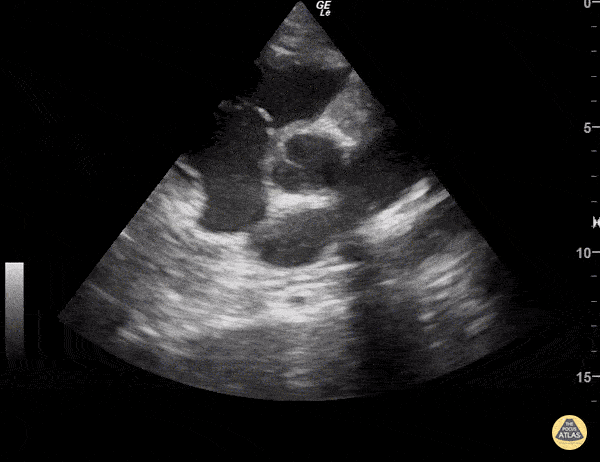

https://www.thepocusatlas.com/valvulopathy

View: Unspecified Parasternal Long Axis Parasternal Short Axis Apical Four-Chamber Subcostal Four-Chamber Subcostal Inferior Vena Cava Right Upper Quadrant Left Upper Quadrant Suprapubic Longitudinal Suprapubic Transverse Subxiphoid Anterior Thoracic Phrenic